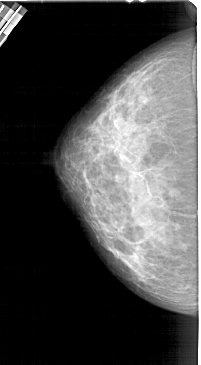

A_1447_1.LEFT_MLO

LEFT_MLO LINES 5491 PIXELS_PER_LINE 3091 BITS_PER_PIXEL 12 RESOLUTION 43.5 NON_OVERLAY